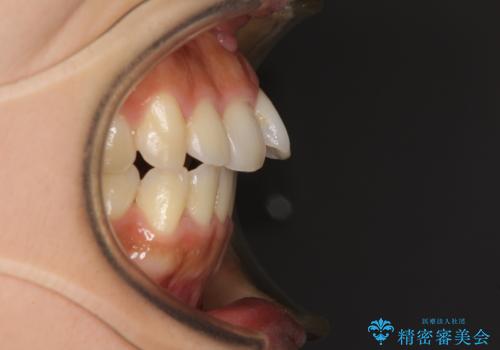

- 飛び出した前歯と口元の突出感を気にして来院された患者様です。

奥歯の咬み合わせを見ると、上顎が下顎に対して相対的に前方にありました。

口元の突出感を改善するためには、上顎臼歯を後方に移動させた咬み合わせにする必要があります。